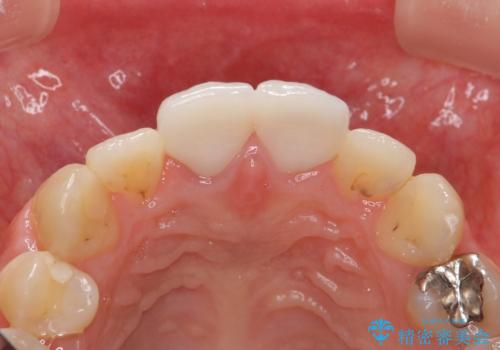

虫歯の徹底的な除去、根管治療を行いセラミック治療に入る前の環境をしっかりと整えたのち審美的なジルコニアセラミックで治療を仕上げました。